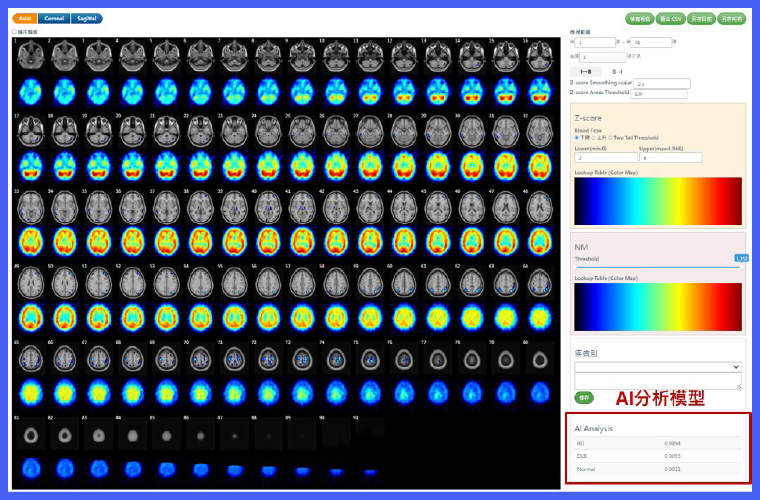

▲系統可依個案年齡自動比對相對應的正常人腦功能影像資料庫,提升分析的準確性與臨床判讀效率。(圖/亞東醫院提供)

國原院近年積極投入智慧醫療領域研發,成功開發腦血流影像異常分析軟體「ECDaim」,可運用於核醫腦部影像判讀,協助臨床醫師偵測腦部退化性疾病。該軟體以院內自建的腦功能常模資料庫為基礎,透過相對腦血流分析與比對,自動突顯細微的異常區域,顯著提升影像解讀的效率與準確度。

為克服跨院影像差異及對照影像不足等挑戰,研究團隊更結合專利技術與機器學習演算法,建立可依年齡調整的常模模板,確保不同儀器間分析結果的一致性。相關技術成果屢獲肯定,其中專利技術更榮獲2025年台灣創新技術博覽會資訊類鉑金獎。

核醫科功能性分子影像能反映失智症病程早期的細微生理變化,是這套智慧判讀系統的核心。亞東醫院核子醫學科主任汪姍瑩醫師分享,AI系統可在資料導入後快速生成半定量Z-score分析報告與三維定位圖,輔助臨床醫師精準辨識腦區血流異常。臨床驗證結果顯示,AI判讀與專家結果一致性高達9成以上,證明人工智慧已成功融入診斷流程。